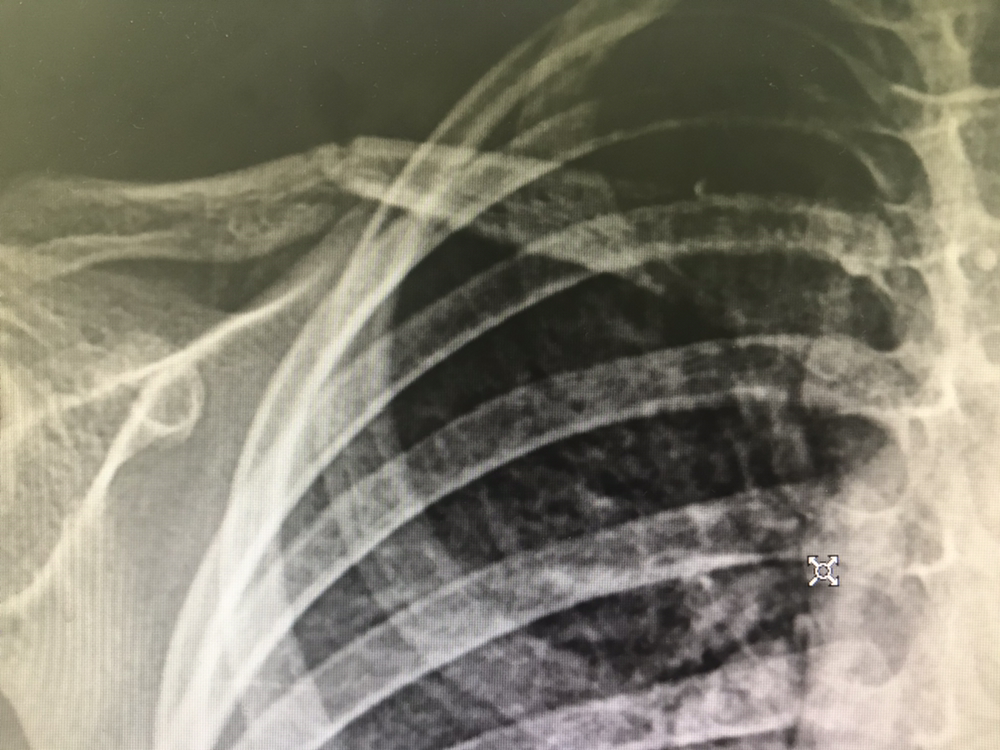

머리 부딪혀 뇌출혈,

다리 꺾여서 골절이

돌연 생기곤 합니다.